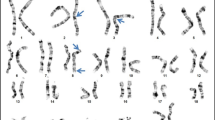

We found EXT1 and EXT2 heterozygous mutations in 28 out 33 (84.9 %) unrelated probands from our cohort. In total, we demonstrated 26 different mutational hits, since two of them were recurrent. Eighteen causative alterations (54.6 %) were identified in EXT1, while ten (30.3 %) were shown in EXT2. The remaining five cases (15.1 %) were negative for both EXT1 and EXT2 mutations. DNA sequencing has allowed for the detection of causative changes in 26 (78.8 %) probands, whereas MLPA showed intragenic copy number changes in two (6.1 %) further cases. Out of 28 molecularly confirmed unrelated probands, six cases (21.4 %) occurred due to de novo mutation while 22 (78.6 %) inherited the disease causing variant from an affected parent. According to HGMD® Professional 2013.4 and LOVD v.2.0 databases, out of 26 different mutations demonstrated in this study, 15 alterations were novel, whereas 11 were previously reported elsewhere (HGMD, Fokkema et al. 2011). Nine out of the 15 novel single nucleotide variants (SNVs) were identified in EXT1 and six in EXT2. For the description of the mutations and their reference to literature data, see Table 2. Out of 28 mutations detected by us, 23 (82.1 %) represented inactivating variants (17 frameshift, three nonsense, three splicing mutations). The remaining causative changes were two intragenic deletions (both in EXT2) and three missense substitutions (all in EXT1).

In keeping with the past reports, EXT1 mutations are usually distributed throughout the entire protein sequence, while EXT2 lesions cluster in the first half of the protein (Jennes et al. 2009). However, in a large Italian cohort described by Ciavarella et al. (2013), 50.1 % of all EXT1 mutations were localized in exons 1 and 2. Our findings based on Polish patients support the hypothesis that there may be an excess of mutations in the first two exons of EXT1. In our cohort, mutation in exons 1 or 2 was identified in ten of 18 (55.6 %) EXT1 mutation carriers, which comprised 30.3 % of our initial cohort (ten probands out of 33). Therefore, we propose that diagnostic screening of HME Polish patients should start with the sequencing of the first two exons of EXT1, followed by sequencing of the rest of the gene. Next, in the case of negative results, we suggest EXT2 sequencing followed by copy number assays for EXT1/EXT2 exons.